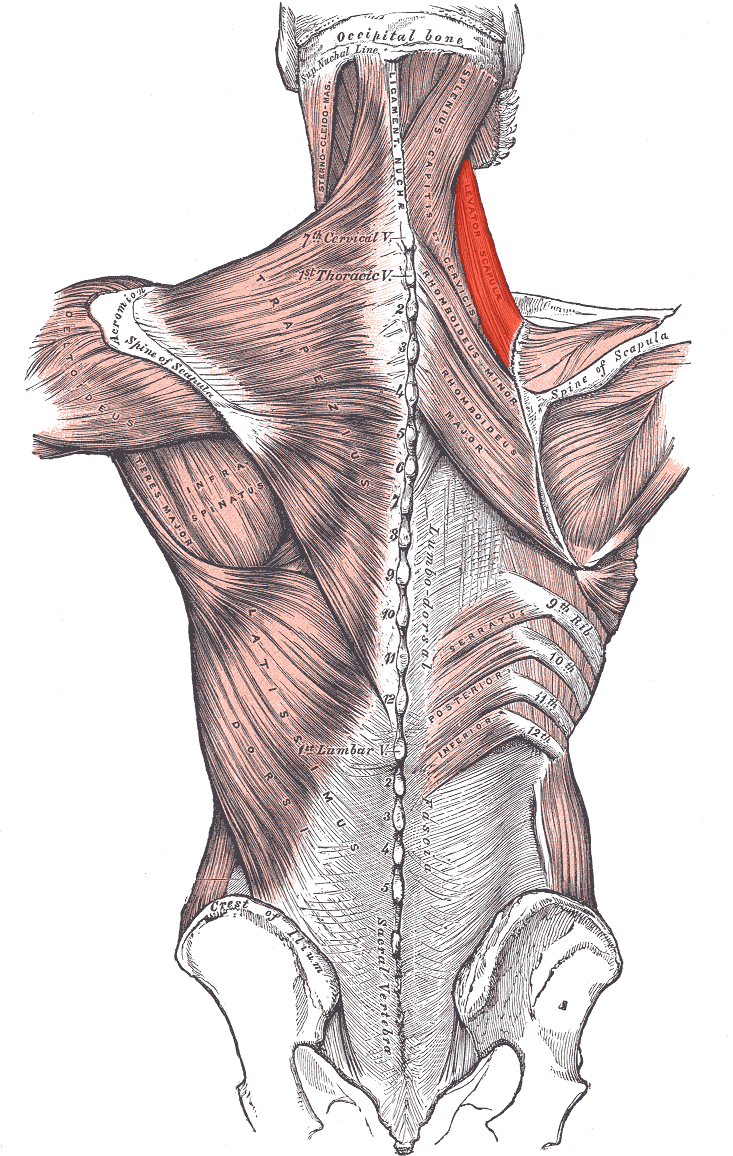

Levator scapulae

Höjning och adduktion av scapula